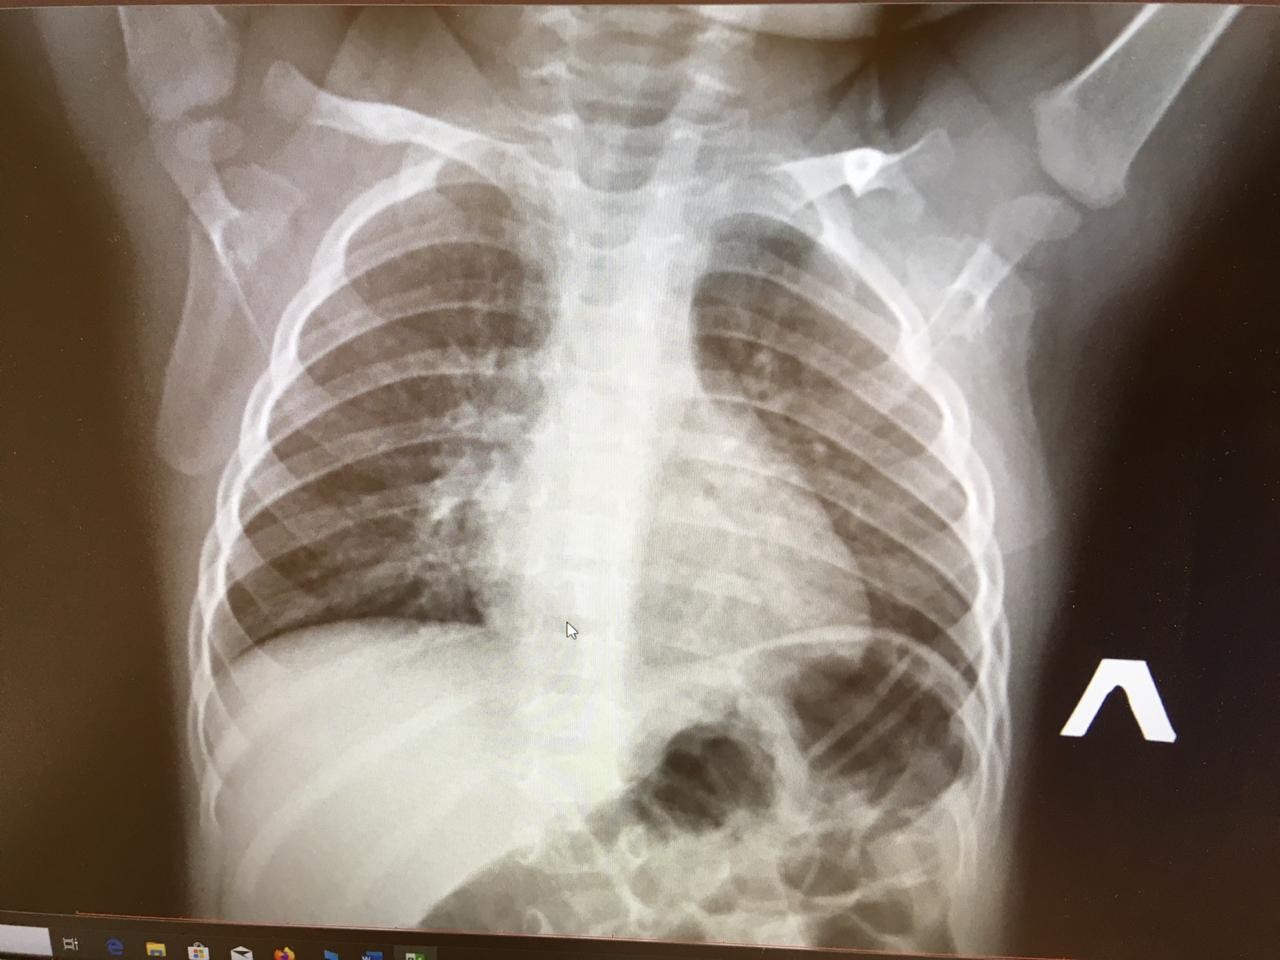

Снимок грудной клетки здорового ребенка: примеры и диагностика

Раздел: Мудрость в объективе